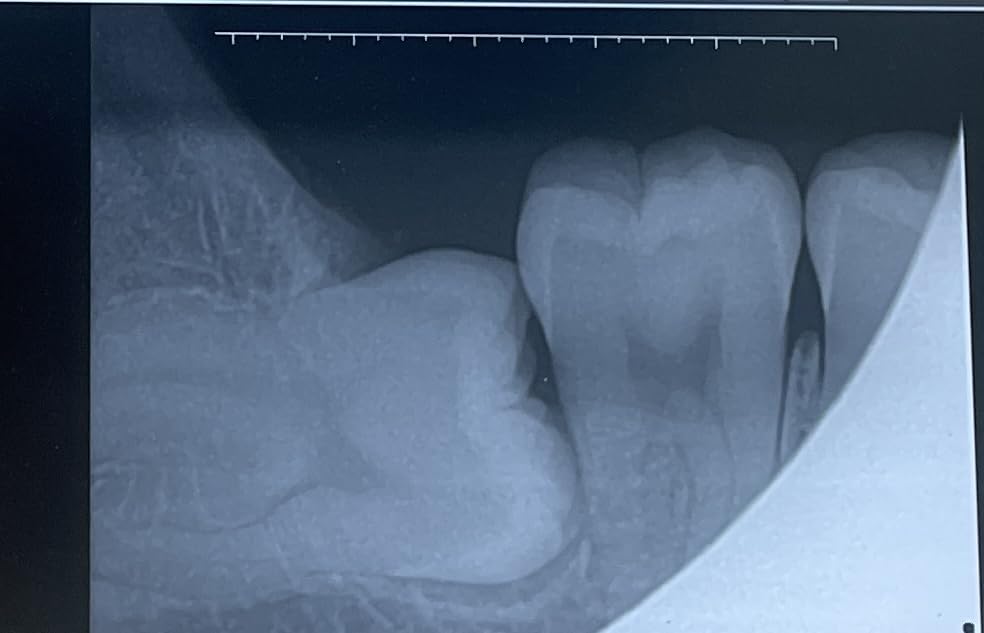

This sensor impressed me with its incredibly fast 3-second image acquisition time. In a busy small practice, every second counts, and being able to capture and display images almost instantly significantly improved my workflow efficiency. The USB 2.0 connection delivered sharp, clear images that made diagnosis straightforward. I tested this sensor with various dental imaging software and found it universally compatible.

The one-hand positioning system is brilliantly designed for stability. During my testing, I appreciated how easily I could position the sensor while maintaining patient comfort. The 16-bit dynamic range produced images with excellent contrast and detail, revealing even subtle pathology. The IP67 waterproof rating gives peace of mind during cleaning and sterilization procedures.

Technical specifications include a dynamic range of 16 bits, which is exceptional for diagnostic imaging. The USB 2.0 interface ensures reliable data transfer to your computer system. The sensor dimensions are compact at 8.3 x 5.9 x 2.6 inches, and at just 12.8 ounces, it’s comfortable for patients to hold in place. The one-click installation software makes setup straightforward even for non-technical staff.

This premium portable unit delivers exceptional image quality thanks to its super high frequency technology operating above 400kHz. During my testing, the difference in image clarity was noticeable compared to standard frequency units. The single-ended solid insulation technology contributes to sharper, more detailed X-rays that make diagnosis more confident. I was particularly impressed by the versatility – this unit works with film, fluorescent plates, and flat panel detectors.

The battery life is outstanding, delivering over 300 exposures per full charge. In a small practice setting, this means you can easily handle a full day’s patient load without worrying about recharging. The technical specs are professional-grade: 60KV tube voltage, 2mA tube current, and exposure times adjustable from 0.01 to 2 seconds. Radiation leakage is minimized below 0.25mGy/h at 1 meter.

What sets this unit apart is the sensor resolution of 12-14lp/mm, which is excellent for diagnostic detail. The USB 2.0 sensor connection ensures fast image transfer to your computer system. The IP67 waterproof rating on the sensor means it can withstand rigorous cleaning protocols. This unit is currently ranked #1 in Dental X-Ray Film Processors, reflecting its popularity among dental professionals.

This complete package pairs the premium XR-A portable unit with a larger digital sensor, making it an ideal all-in-one solution for small practices. The big sensor offers a 2.5x3cm imaging area, which is significantly larger than standard sensors. During my testing, this larger area meant fewer retakes and better coverage for adult patients. The 5mm sensor thickness is slim enough for patient comfort while maintaining durability.

The technical specifications match the premium XR-A unit: super high frequency technology above 400kHz, 60KV tube voltage, and 2mA tube current. What makes this package special is the inclusion of both sensor size options – you get the standard 2.1×2.1cm sensor for pediatric patients and the larger 2.5x3cm sensor for adults. This versatility is invaluable for small practices serving diverse patient populations.

The sensor connects via USB 2.0 for fast image transfer, and the IP67 waterproof rating ensures it can withstand rigorous cleaning. The 3-meter cable is extendable if needed, providing flexibility in operatory setup. Sensor resolution of 12-14lp/mm delivers diagnostic-quality images that reveal even subtle pathology. Like other units in this series, you get over 300 exposures per full charge.